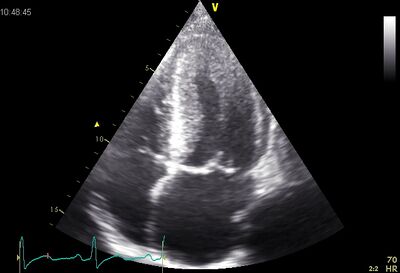

DCM01.jpg

Dilated LV on AP4CH